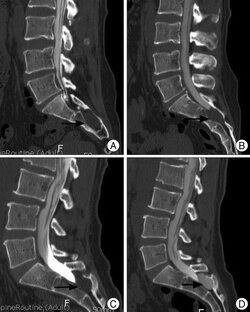

Виды сколиозов «Сколиоз» – боковое искривление позвоночника, дугообразное смещение некоторых позвонков в сторону от средней линии позвоночника. Можно выделить следующие основные формы сколиозов (см. рис.): А) Рефлекторный сколиоз из-за одностороннего сокращения болезненно напряженных мышц. Обратите внимание на то, что межпозвонковые хрящи только сплющиваются. Б) Истинный сколиоз из-за нарушений, деформации структуры тканей позвоночника или межпозвонкового хряща. 1. Область рефлекторного сокращения болезненно напряженных мышц; 2...